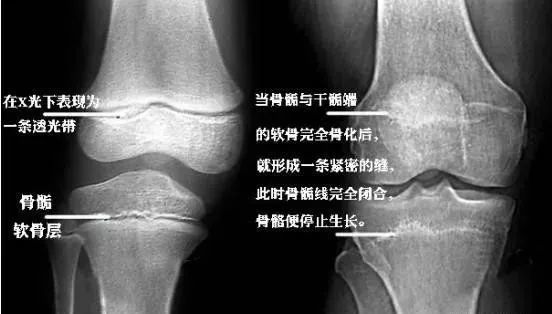

二,什么是骨骺线闭合 骨骺线是指长骨干骺端与骨骺之间的一层软骨

在骨骺与干骺端之间有一块软骨,会随着年龄的不断增长而逐渐变短,在

使长骨不断加长;长骨成熟后,骺板活动停止,自身完全骨化,称为「干骺